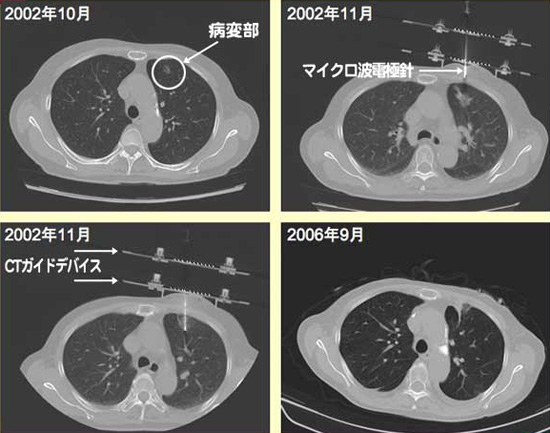

1例だけ症例を提示いたします。

85歳の女性で糖尿病、高血圧、心不全、リュウマチ、慢性腎不全を治療するために外来通院していました。2002年10月に偶然、左上葉に早期癌(野口分類のタイプBに相当 papillary adenocarcinoma)が発見され、11月にマイクロ波治療を行い、2006年9月の最終CTで再発なく現在も健在で通院中です。